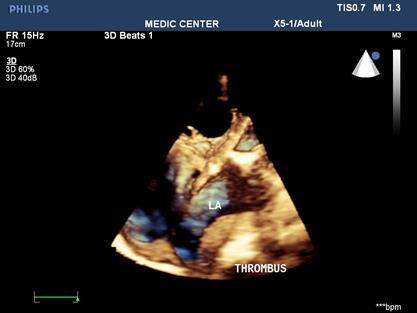

Because patients often presented late in Hospitals, their Wilkins score usually is high (68% with Wilkins score is superior to 8). Especially, LAA thrombus, even small size, furthermore, can be detected more clearly on RT- 3DTEE. Volume and mobility of LAA thrombus appreciated better on 3DTEE.

Detection LA and LAA thrombus by RT-3DTEE is more sensitive than 2DTEE with X-plane mode and 3 D Zoom only are avaible in 3DTEE.

Figure 5. 3D Zoom imaging demonstrating LAA with thrombus inside

Figure 7. LAA three dimensional view with thrombus attached to LAA wall

Figure 8. 3DTEE with icrop function shows thrombus attached to LA wall